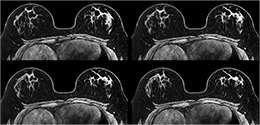

Wann ist eine Kernspintomographie sinnvoll?

Die Mamma-MRT ist ein sehr sensitives Verfahren, das heißt Brustkrebsknoten können sehr empfindliche dargestellt werden. Allerdings kann die Mamma-MRT Befunde auch überschätzen, scheinbar bösartige Befunde stellen sich dann doch als gutartig heraus. Sie wird hauptsächlich zur Abklärung komplexer Sachverhalte gemeinsam mit Mammographie und Ultraschalluntersuchung eingesetzt.

Die Kernspintomographie der Brust (MRM, Mamma-MRT) ist ein Verfahren ohne Strahlenbelastung, aber es muss immer ein Kontrastmittel eingesetzt werden. Die Untersuchung wird in Bauchlage in der Kernspinröhre durchgeführt und dauert etwa 20 Minuten. Falls Sie unter Platzangst leiden, kann dies durch vorherige Gabe eines Beruhigungsmittel gemindert werden. Die gesetzlichen Krankenkassen übernehmen die Kosten nur in Ausnahmefällen und nach vorheriger Anfrage.